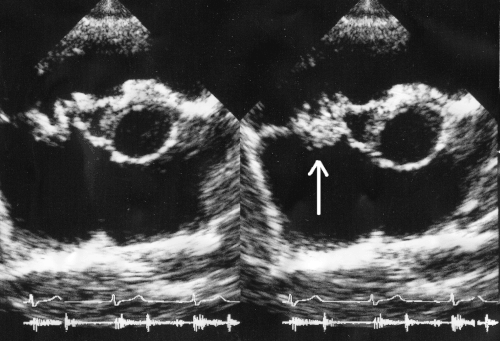

-

Ultrasound showing infectious endocarditis[48]

Ultrasound showing another case of infectious endocarditis[49]